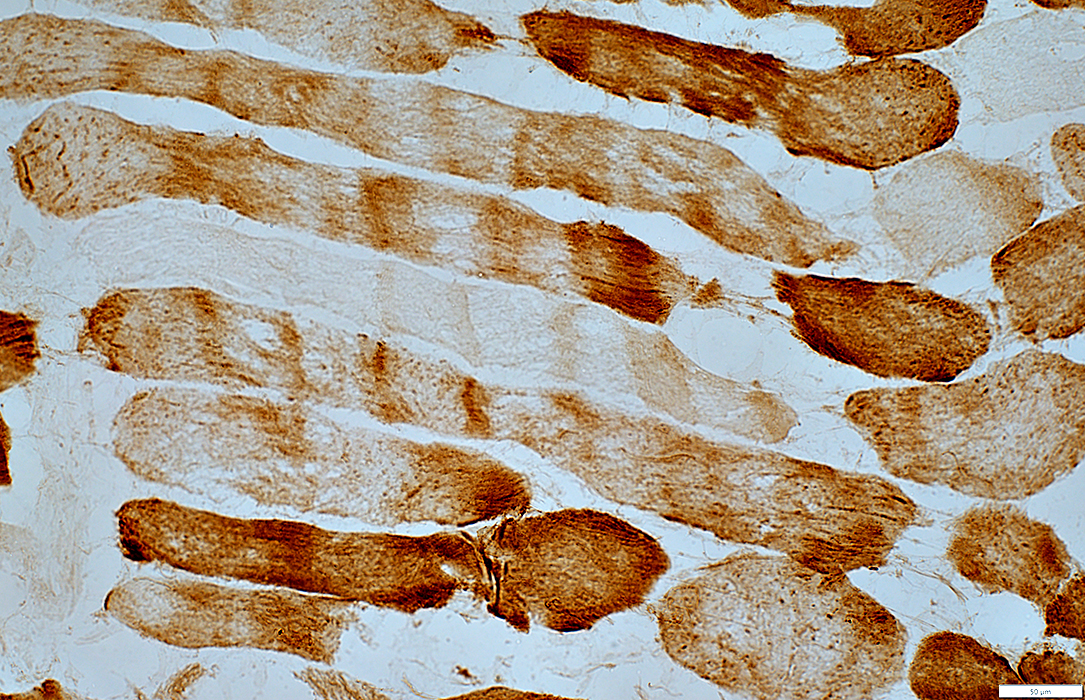

Succcinate Dehydrogenase (SDH)

Muscle fibers have increased staining

SDH stain

Scattered muscle fibers with increased staining

Mitochondria appear large